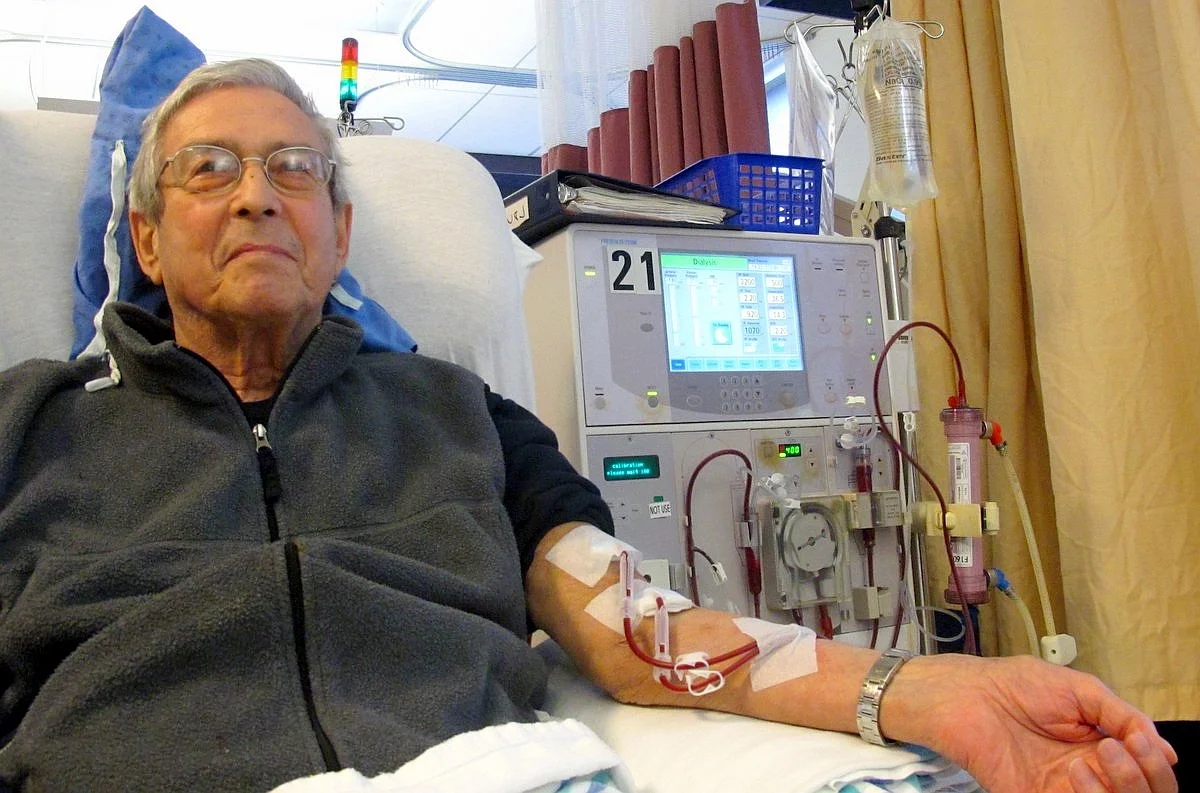

Kidney Dialysis

Our Dialysis Services offer advanced, safe, and comfortable treatments to cleanse blood, balance fluids, and support kidney health.

Dialysis Treatment Explained: Restoring Balance to Your Body

Dialysis is a medical treatment that helps filter the blood to remove toxins and excess